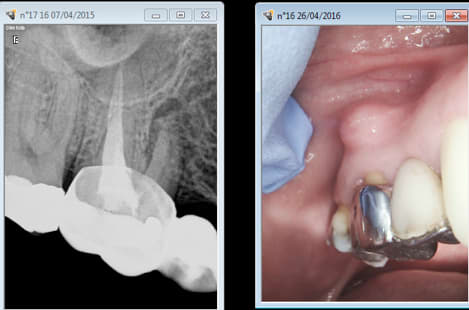

patiente qui consulte pour une cellulite due à 42 avec une image terrifiante

genre le truc qu'on hesité a garder pour ne pas avoir de soucis

traitement classique après antiothérapie avec jaillissement de pus ... 5 minutes de sterildent ... canaux parfaitement secs ...

obturation dans la scéance , et 14 mois après CCM (qu'on ne me parle pas de resorpion externe : artefact)